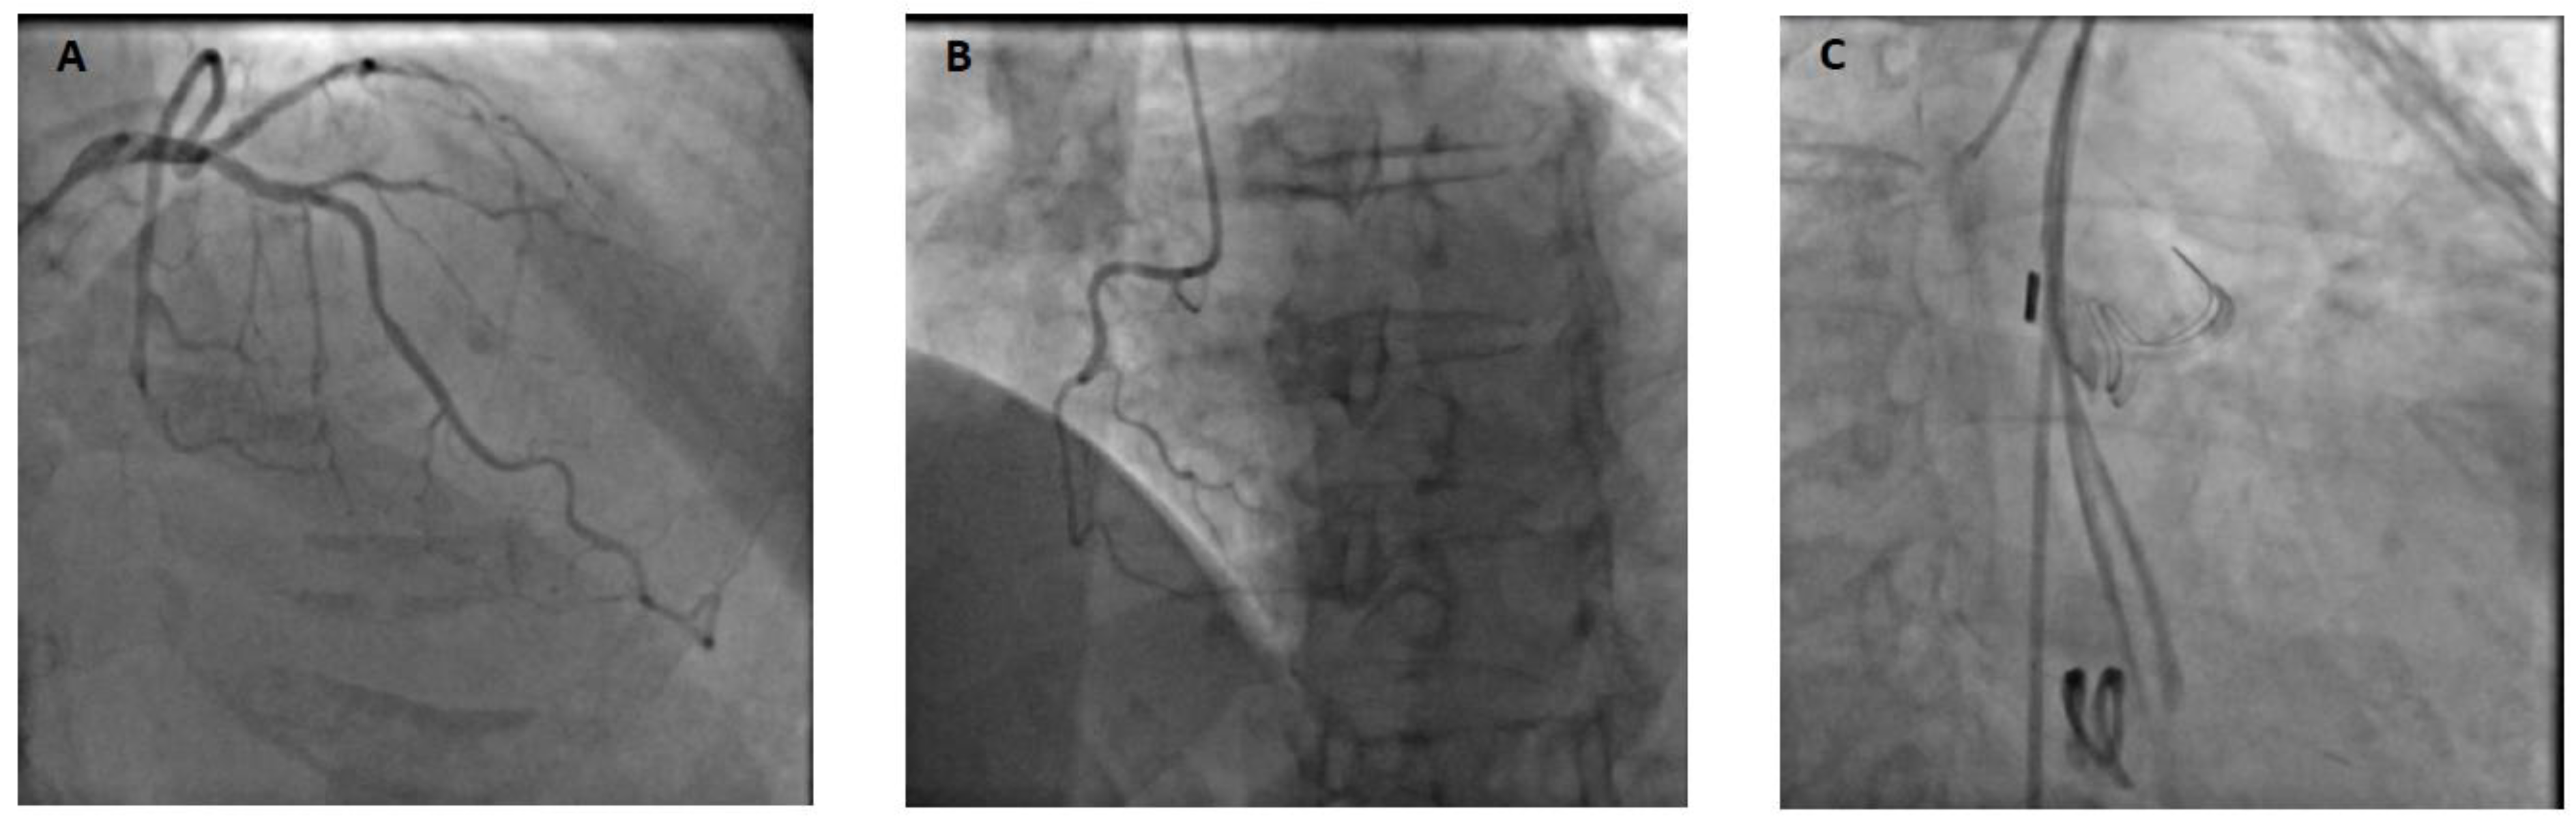

A 69-year-old patient without any relevant past medical history underwent aortic valve replacement in the context of a bicuspid valve and severe aortic stenosis. The surgery was uneventful, and the patient was weaned from cardiopulmonary bypass successfully with a minimal amount of vasopressor support and under transesophageal echocardiography (TEE) guidance. However, while surgical hemostasis was performed, the patient became progressively unstable and required increased doses of vasopressors and inotropes. After sternal closure, another TEE examination was urgently performed and showed severe dilation and global akinesia of the right ventricle. The surgical and anesthesiology team decided to proceed to a percutaneous coronary intervention (PCI). Angiography showed complete occlusion of the right coronary artery (Figure 1); however, the artery was not technically amenable to percutaneous treatment. The patient was transferred to our tertiary ECMO center in critical condition. Indeed, on arrival, the patient presented with profound CS refractory to optimal medical management (SCAI E). VA-ECMO was immediately initiated, complicated by a brief cardiac arrest during cannulation (bilateral femoral cannulation: arterial cannula was inserted on the left and venous cannula on the right side). Due to an ischemic time of more than 8 hours, the small caliber of the right coronary artery and left coronary dominance (Figure 1), it was decided by a multidisciplinary team (cardiac critical care, cardiology and cardiac surgery consultants) to not proceed with emergent coronary artery bypass graft surgery in a patient presenting with multiple organ failure (MOF). Anticoagulation was withhold during the initial 48-hour period. This decision was made because the patient presented rapidly after admission a tamponade along with a hemorrhagic shock resulting from bleeding at the aortotomy site. Subsequently, a conventional anticoagulation regimen with unfractionated heparin was initiated and gradually increased towards therapeutic anticoagulation levels (Anti-Xa 0.3-0.5 IU/ml). The patient's anticoagulation status was closely monitored through Anti-Xa assay measurement.

Figure 1. Preoperative coronary angiography reported a Left dominance Panel A & B). Postoperative coronary angiography confirmed an ostial right coronary artery occlusion (Panel C) LCA: Left coronary artery, RCA: right coronary artery.